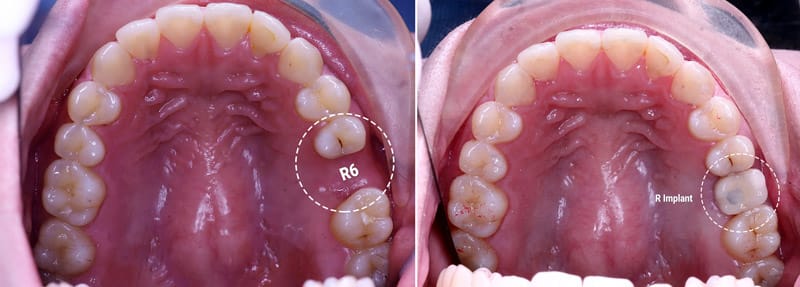

Cấy Ghép Implant cho răng số 6 bị mất

Mất răng số 6

Tác hại việc mất răng 6